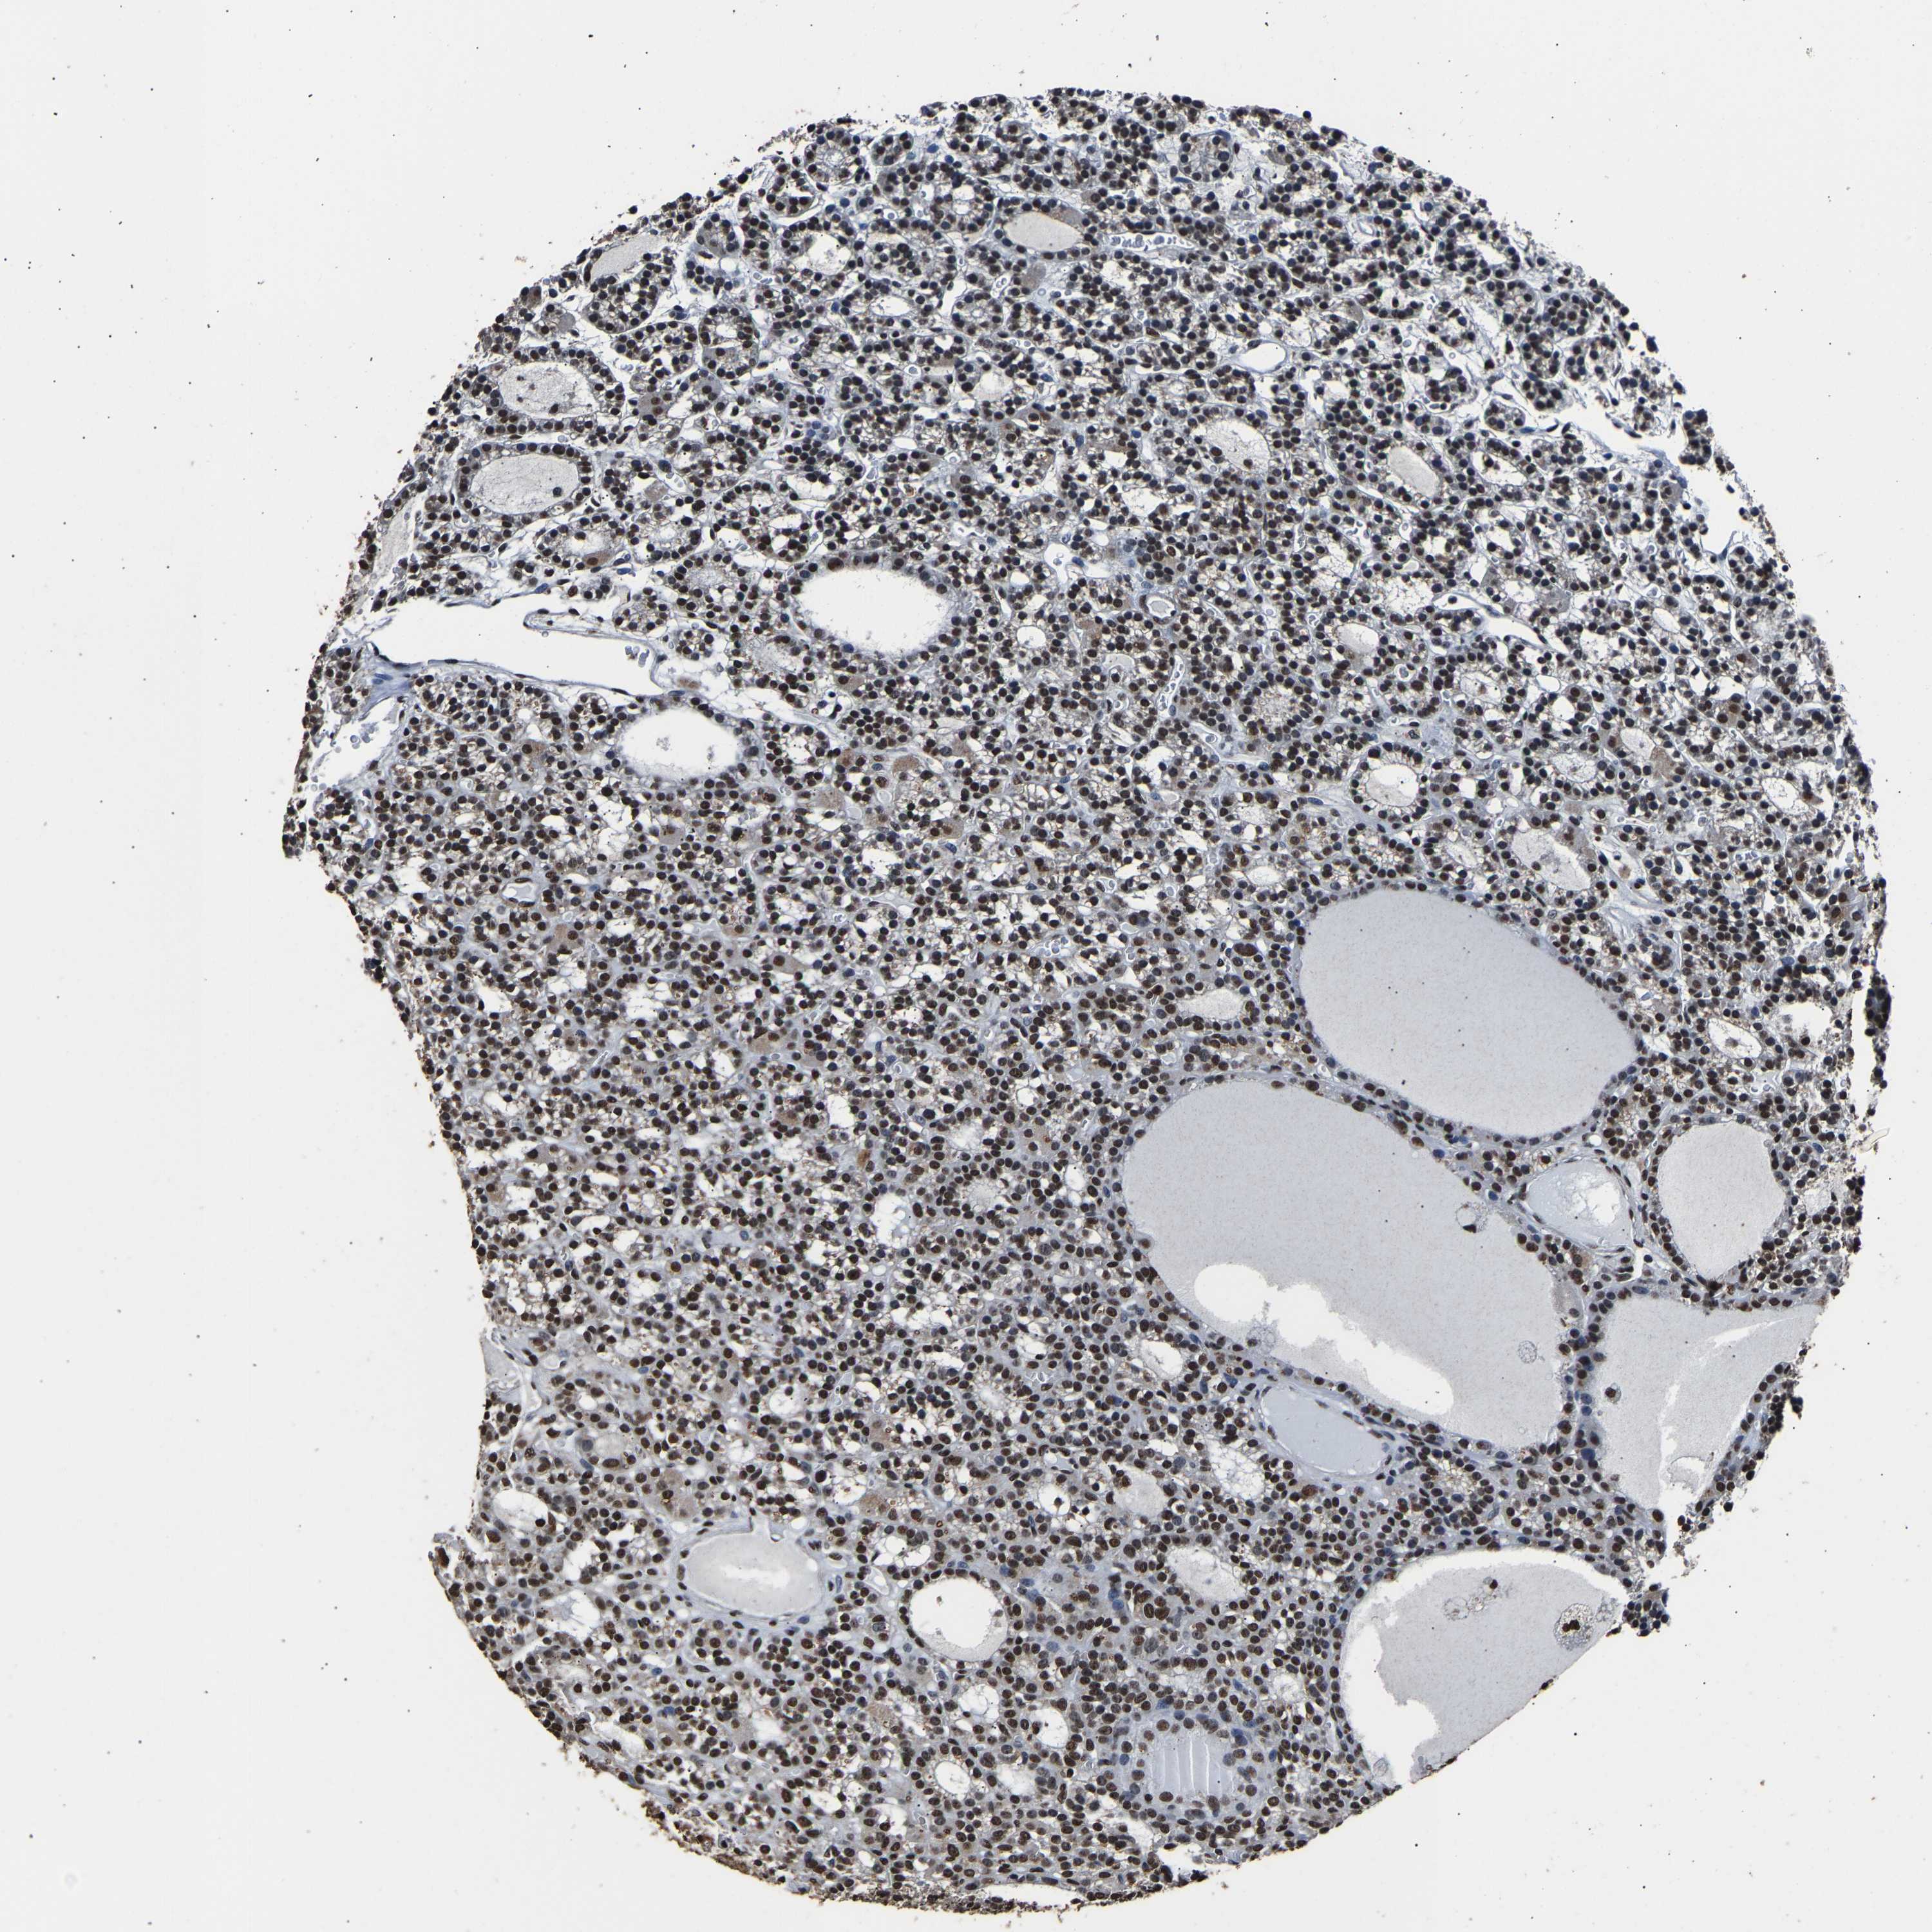

TISSUE PRIMARY DATA PARATHYROID GLAND Show tissue menu

PARATHYROID GLAND - Antibody stainingi

Antibody staining in the annotated cell types in the current human tissue is reported as not detected, low, medium, or high, based on conventional immunohistochemistry profiling in selected tissues. This score is based on the combination of the staining intensity and fraction of stained cells.

Each image is clickable and will lead to virtual microscopy that enables deeper exploration of all samples and also displays staining intensity scores, fraction scores and subcellular localization as well as patient and tissue information for each sample.

Antibody HPA016832Antibody HPA020076Antibody CAB001969

Glandular cells HighHighHigh